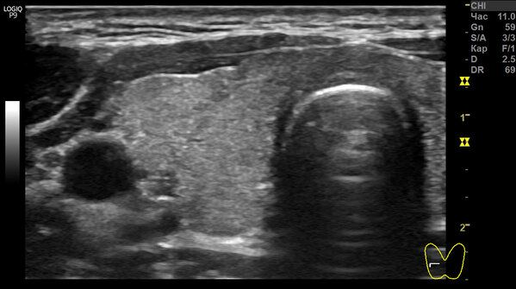

Зачем делать УЗИ щитовидной у обычного "узиста"?